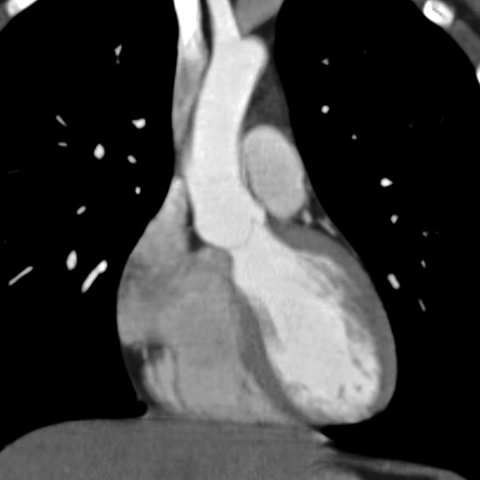

Normal Heart (CT) [3 of 6]